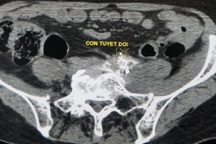

Vì thế, các bác sĩ đã hội chẩn quyết định điều trị giảm đau cho bệnh nhân bằng phương pháp diệt đám rối thần kinh thân tạng. Bệnh nhân được gây tê vùng can thiệp, dưới hướng dẫn của máy cắt lớp vi tính bác sĩ can thiệp điện quang đưa kim đi từ sau lưng vào vị trí đám rối thần kinh thân tạng, bơm cồn tuyệt đối để diệt hạch thần kinh. Chỉ trong vòng khoảng một tiếng thực hiện kỹ thuật này, tình trạng đau của bệnh nhân đã được cải thiện đáng kể. Bệnh nhân gần như hết đau, ăn uống tốt và ngủ được.